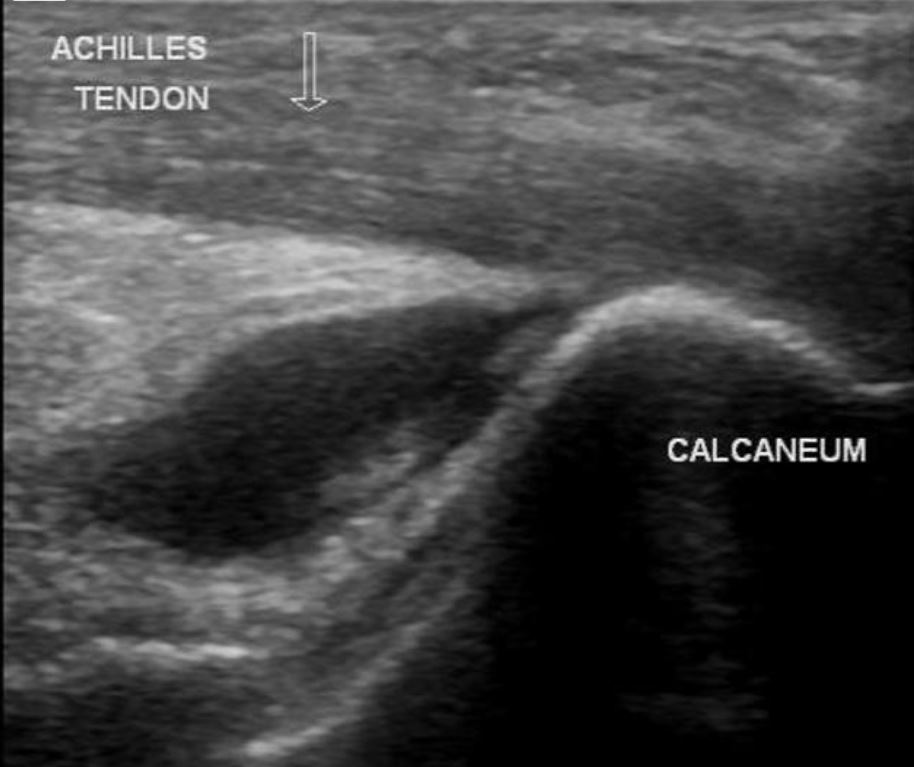

Situate vicino al tendine di Achille si trovano due Borse. La borsa anteriore è chiamata Borsa Retrocalcaneare. Si trova tra l’osso del calcaneare e il tendine di Achille. C’è anche una borsa superficiale, chiamata Borsa Calcaneare sottocutanea. Si trova tra la superficie della pelle e la porzione inserzionale distale del tendine di Achille.

L’infiammazione di una o entrambe queste borse è chiamata borsite del tendine d’Achille. Quando le borse si irritano per un uso eccessivo o ripetitivo o per lesione diretta, producono liquido extra che ne distende le pareti. La borsite può anche essere causata secondaria a determinate infezioni, come lo stafilococco; gotta o pseudogotta o artrite reumatoide.

L’Ecografia consente innanzitutto di fare diagnosi evidenziando la Borsa Infiammata e distesa dal liquido infiammatorio, confermando il sospetto clinico, ed nel caso della terapia infiltrativa funge da guida consentendo di seguire in tempo reale il percorso dell’ago dalla cute alla Borsa e l’iniezione intrabursale del farmaco.